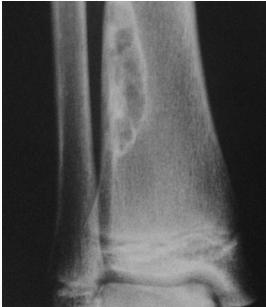

Aneurysmal Bone Cyst

- Child - young adult

- Metaphysis of long bone

- X-ray:

- Well-defined cyst

- Trabeculated

- Eccentrically placed

- Ballooning

- Bloody content

- Treatment:

- Curettage and bone graft

- Metaphysis, Eccentric